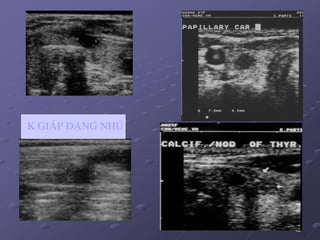

a/. Car. daïng nhuù: 75-90%, tieân löôïng toát, moät hay ña oå,

nhaân phaùt trieån raát chaäm, di caên xa hieám vaø di caên haïch sôùm

(aùi haïch). Laø ung thö giaùp duy nhaát ôû treû em, nöõ > nam. 1 soá

tröoøng hôïp coù haïch coå di caên do ung thö giaùp nhöng khoâng

thaáy nhaân giaùp treân ñaïi theå vaø SA. Khi nhaân kích thöôùc lôùn,

thuøy coøn laïi deã bò ung thö neân caàn caét giaùp gaàn troïn.

 86,7% laø nhaân ñaëc echo keùm, khi lôùn hôn 1 cm nhaân trôû

neân khoâng ñoàng nhaát, giôùi haïn khoâng roõ, 50% coù vi voâi hoùa,

ít thaáy ñöôïc hình daïng nhuù trong nang.

K GIAÙP DAÏNG NHUÙ